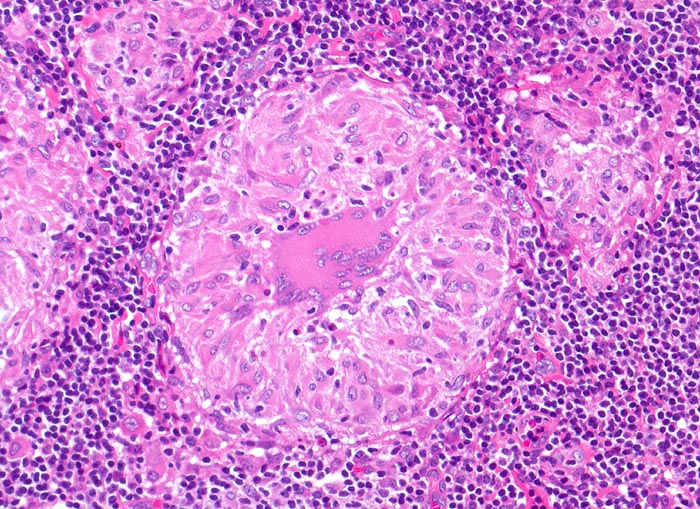

Sarkoidosegranulome bestehen aus Epitheloidzellen mit einem peripheren Lymphozytensaum. Mehrkernige Riesenzellen, meistens solche vom Langhans-Typ mit hufeisenförmig angeordneten Kernen und Asteroidkörperchen (> 4173) können zusätzlich vorhanden sein. Diese Granulome enthalten meist keine Nekroseherde (=produktives Granulom). Man findet diesen Granulomtyp hauptsächlich in Lymphknoten, aber auch in inneren Organen und in der Haut. Die Sarkoidosegranulome zeigen in späteren Stadien eine charakteristische perigranulomatöse und die Granulome septierend unterteilende Fibrose (> 4015).

Morphologische Merkmale:

• Konfluierende Granulome aus grossleibigen Epitheloidzellen.

• Wenige mehrkernige Riesenzellen.

• Kleinere Nekroseareale im Zentrum grösserer Granulome. (Die Nekrosen sind untypisch für die Sarkoidose, können aber bei grossen Granulomen gelegentlich vorkommen).